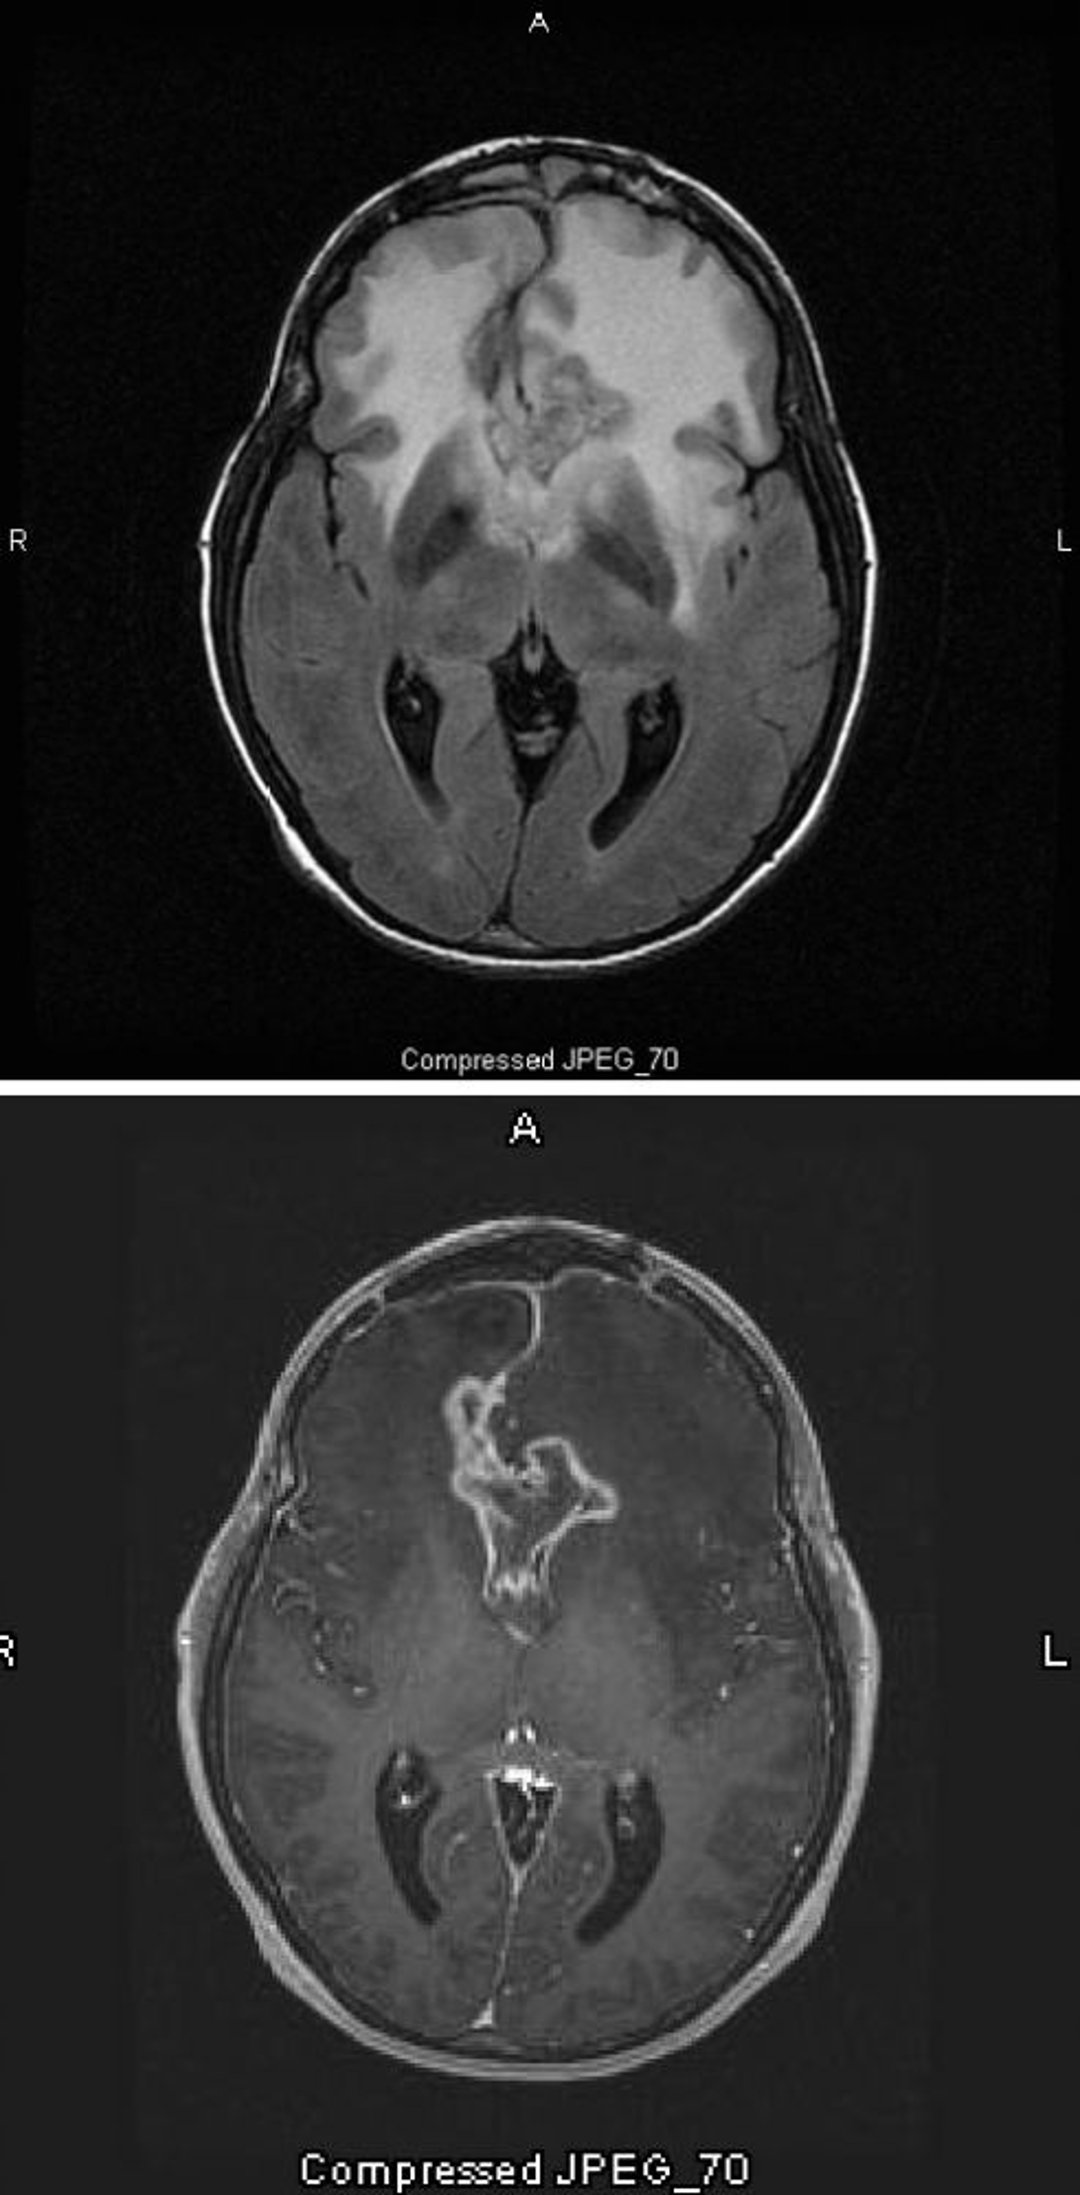

膠芽腫

MRIのT2-FLAIR像(上)には,異型度および悪性度が最も高い星細胞腫である膠芽腫の周りに大きな両側性の白い(高信号)領域が認められる。この種類の膠芽腫は,腫瘍周囲の白い高信号域が蝶の羽形に見えることから特にbutterfly gliomaと呼ばれ,この変化は脳浮腫によって引き起こされる。MRIのT1強調画像(下)では,腫瘍の縁が造影されている(リング状造影効果)。浮腫はT1上で暗い(低信号)領域として現れる。

Images courtesy of William R.Shapiro, MD.